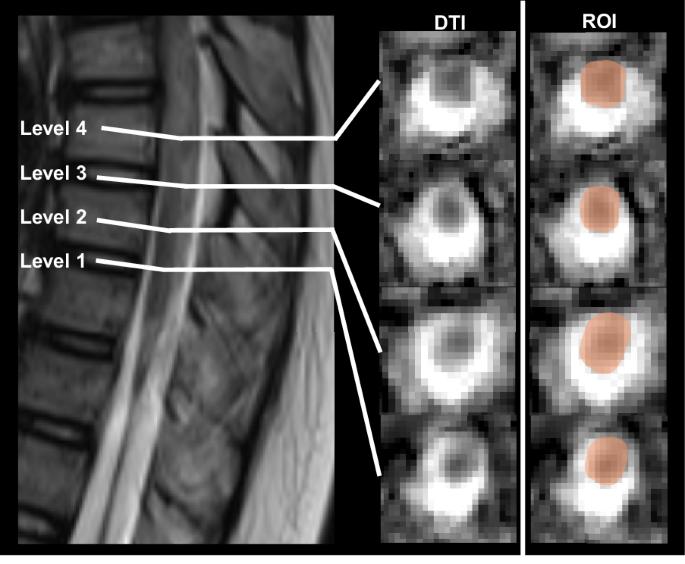

Cross-sectional study. This study investigates changes in spinal DTI metrics above lesion in children with spinal cord injury without fracture or dislocation (SCIWOFD), aiming to assess DTI’s potential as a diagnostic and evaluative tool for SCIWOFD in children. Xuanwu Hospital, Capital Medical University, China; Beijing Key Laboratory of Magnetic Resonance Imaging and Brain Informatics, China. This study included 18 children with SCIWOFD and 12 typically developing (TD) children. SCIWOFD children underwent International Standards for Neurological Classification of Spinal Cord Injury (ISNCSCI) assessments and MRI with axial spinal cord DTI. DTI data were processed with Diffusion Toolkit and TrackVis, with four levels above the lesion (Level 1 to Level 4). Spinal DTI metrics were extracted, and statistical analysis was performed using multiple linear regression and Pearson correlation. Compared to the TD group, the SCIWOFD group displayed significant changes in DTI metrics at four spinal cord levels. At level 1, FA decreased (p < 0.000), while MD (p < 0.000), AD (p = 0.007), and RD (p < 0.000) increased. Levels 2 and 3 showed decreased FA (level 2: p < 0.000; level 3: p = 0.001) and increased MD (level 2: p = 0.001; level 3: p = 0.029) and RD values (level 2: p < 0.000; level 3:p = 0.001). At level 4, FA decreased (p < 0.000), while RD increased (p = 0.009). At level 1 in the SCIWOFD group, MD (r = −0.534, p = 0.022) and RD (r = −0.569, p = 0.009) correlated with sensory scores. Spinal DTI metrics above the lesion in children with SCIWOFD exhibit gradient changes, with a statistically correlation between the DTI metrics at the rostral edge of the lesion and ISNCSCI sensory scores. DTI metrics may serve as stable, objective indicators for assessing SCIWOFD in children.